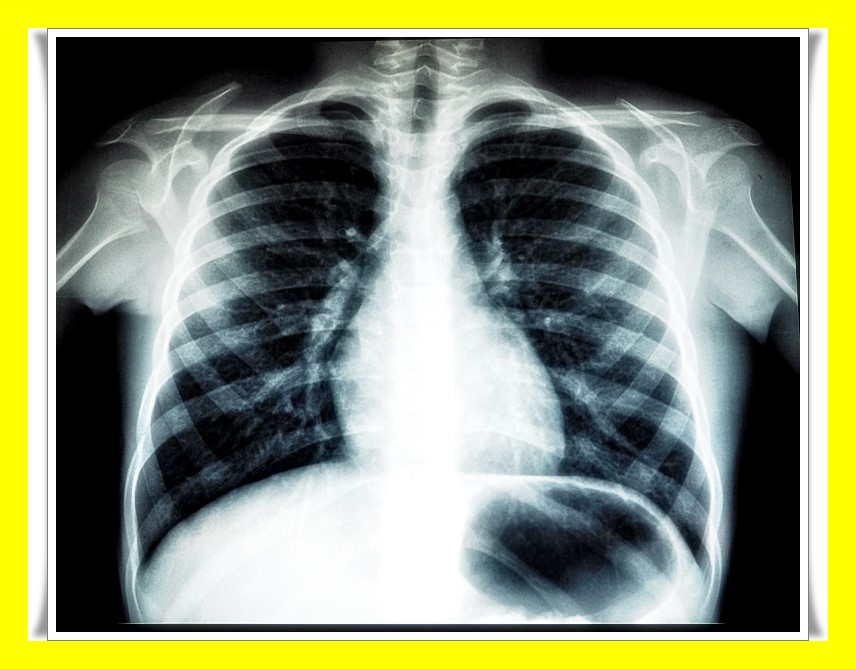

이렇게까지 일상생활이 불가능해지기 전에 병원을 방문하는 것이 최우선인데요. 통풍 진단의 경우, 엑스레이를 촬영하여 관절에 염증이 있는지 확인합니다. 그리고 피검사를 통해 관절 염증 수치 등을 확인하는 방법을 사용합니다.